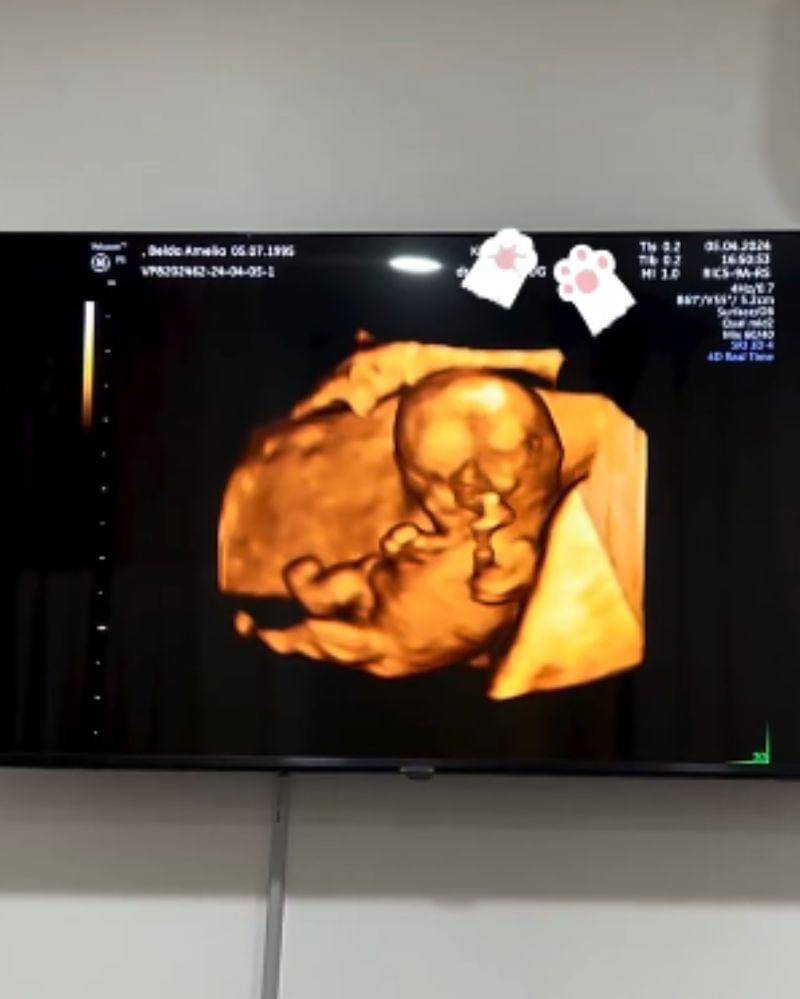

Dokter kandungan Andika Widyatama dan istrinya yang juga seorang dokter dan selebriti internet, Belda Amelia, belum lama ini membagikan kabar bahagia. Keduanya bakal dikaruniai momongan. Yang menarik, Andika Widyatama yang berprofesi sebagai dokter kandungan-lah yang langsung melakukan pemeriksaan pada istrinya.

Di tengah pemeriksaan kehamilan pertamanya, terlihat Belda dan Dika tak dapat menutupi rasa bahagia mereka. Tentu saja momen ini terasa semakin spesial karena Belda diperiksa langsung oleh suaminya sendiri.

Pasangan Belda Amelia dan Andika Widyatama baru saja membagikan kabar kehamilan pertamanya di Instagram. Cerita pasangan ini jadi semakin menarik lantaran pemeriksaan kehamilan Belda dilakukan langsung oleh sang Suami yang berprofesi sebagai dokter kandungan.

Pada video yang diunggah dr. Belda, terlihat ia dan dr. Dika begitu bahagia dan terharu karena akhirnya segera memiliki momongan. Keduanya bahkan saling berpelukan ketika mengetahui bahwa istrinya tengah mengandung.